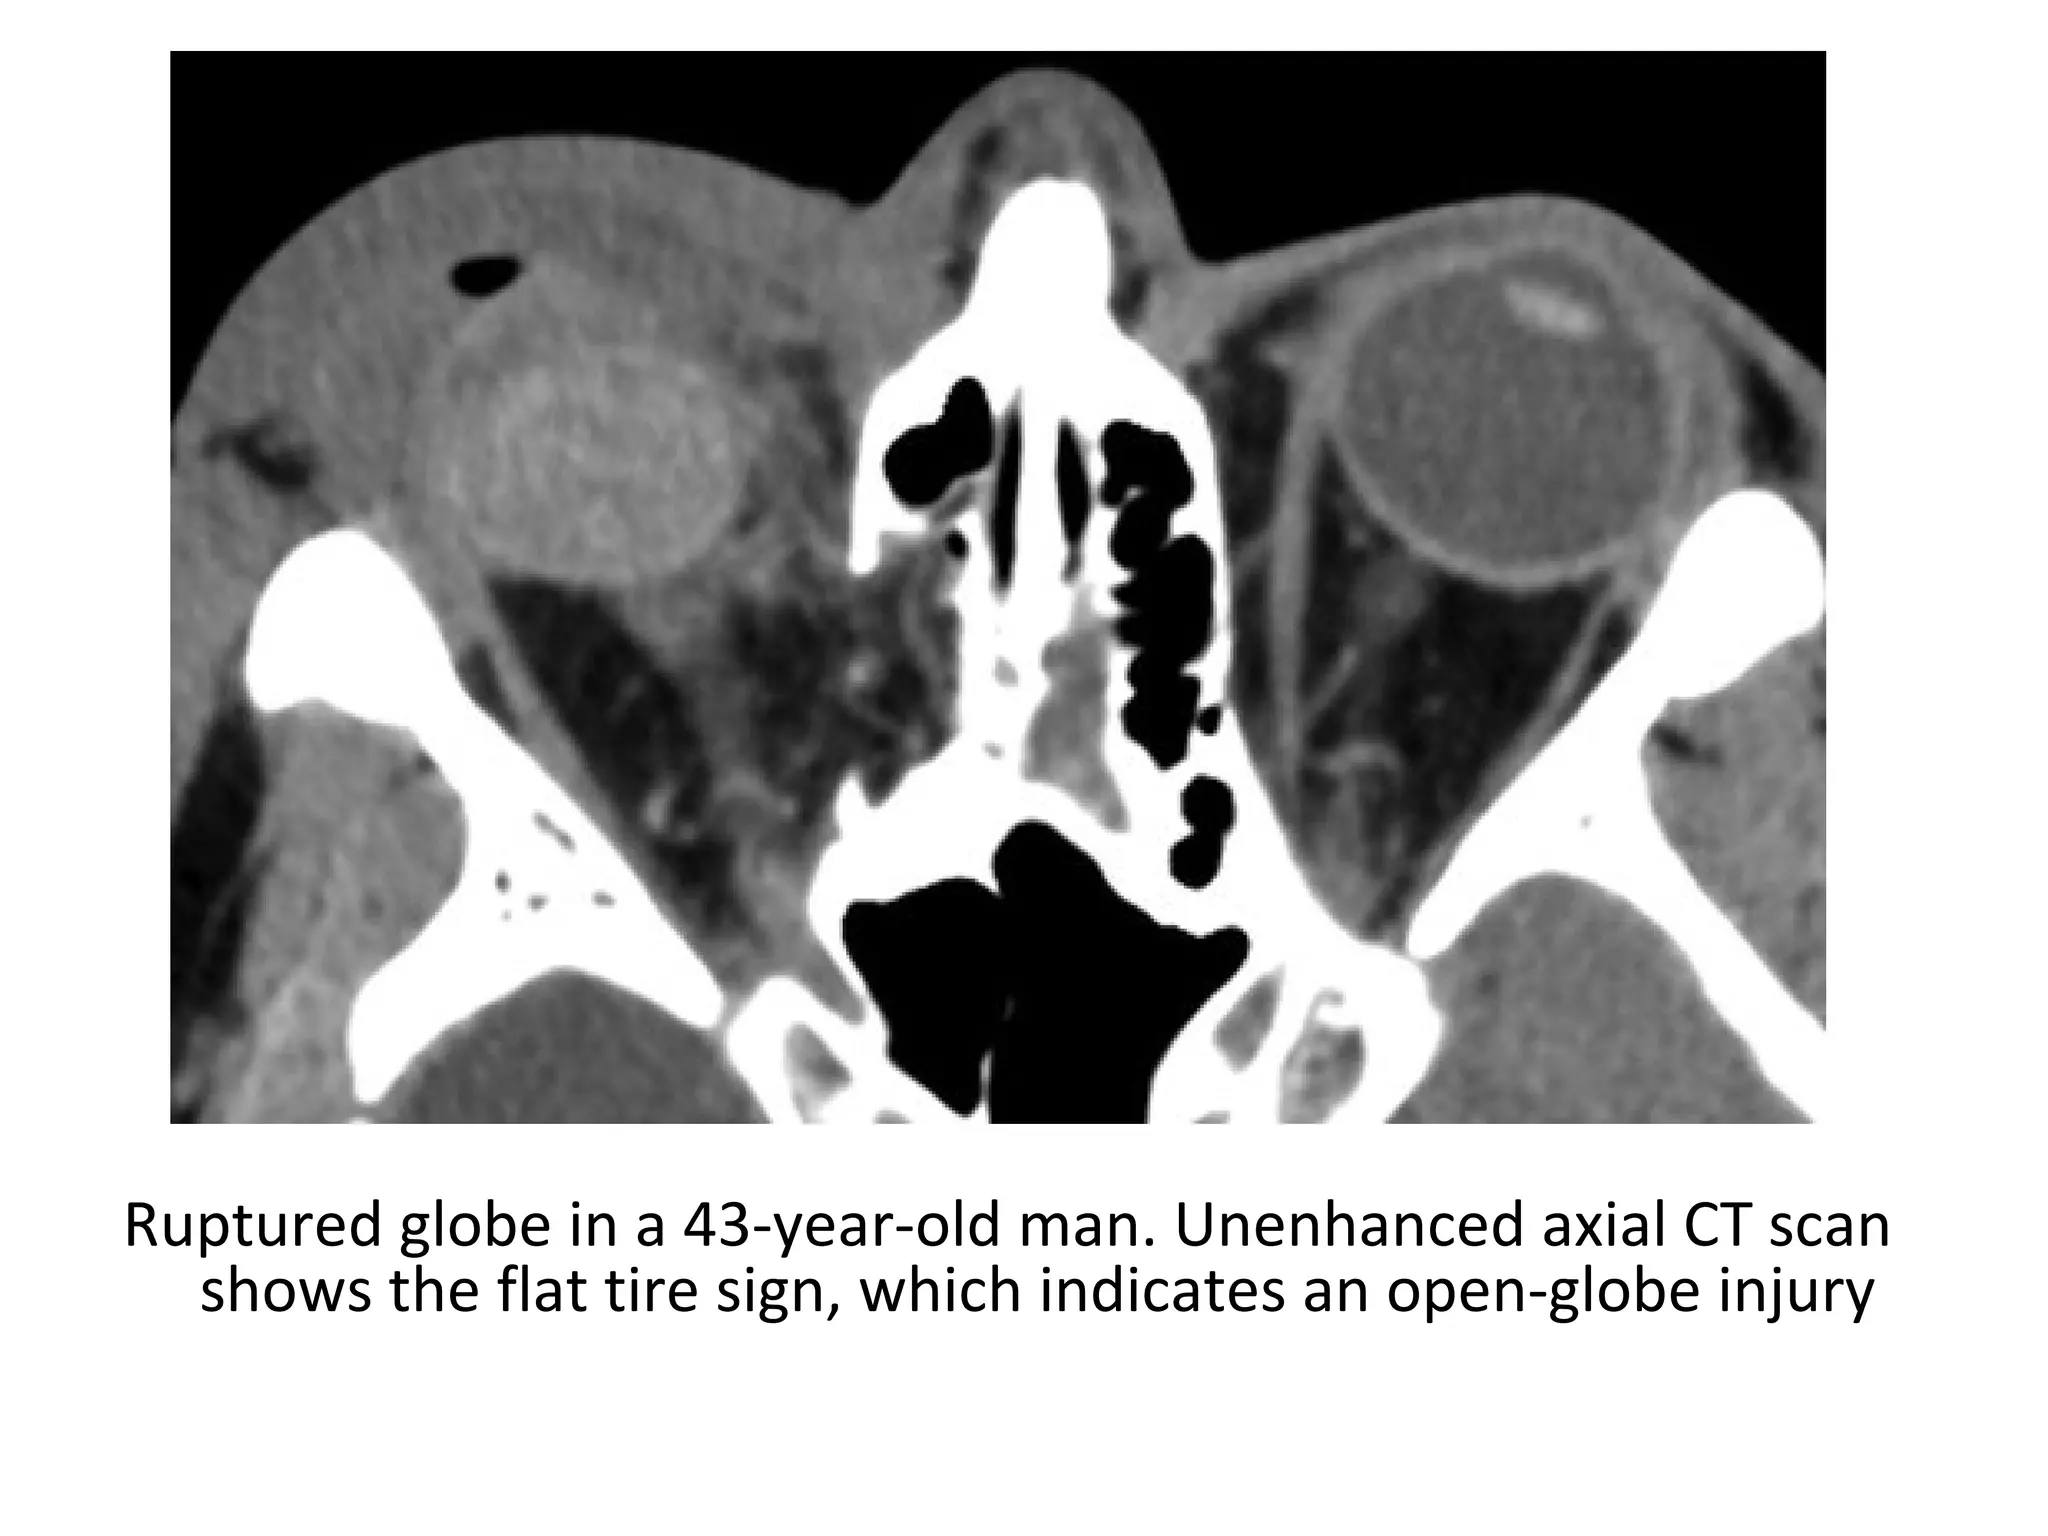

Ruptured globe in a 43-year-old man. Unenhanced axial CT scan

shows the flat tire sign, which indicates an open-globe injury